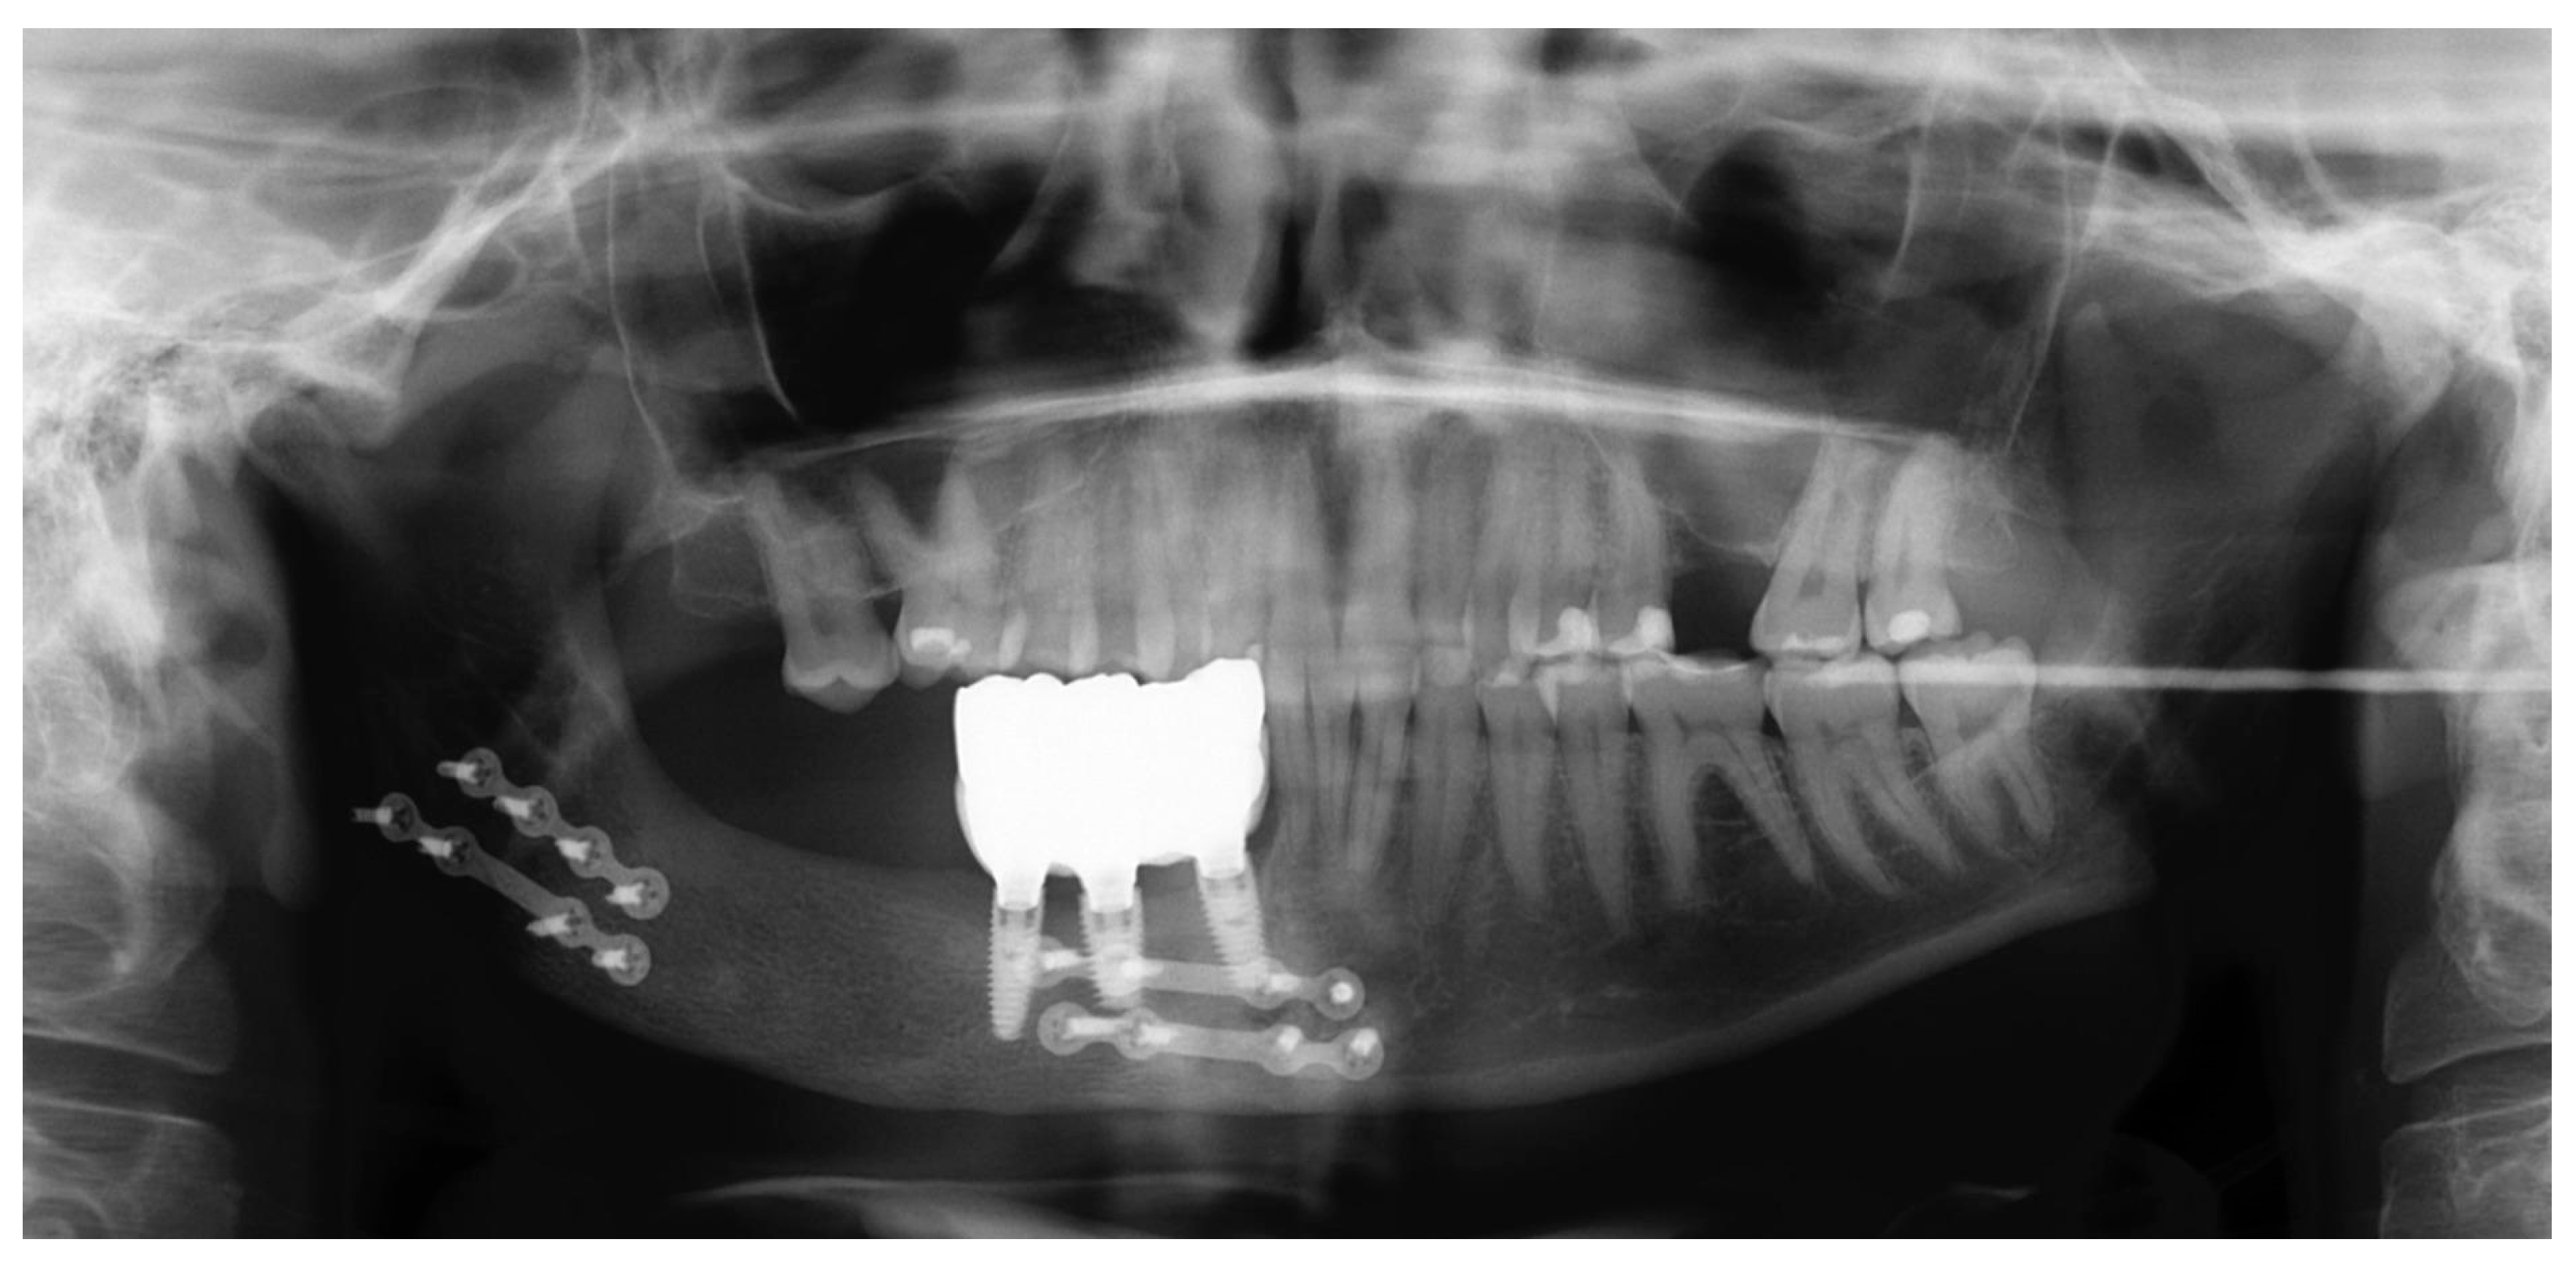

2.4. Follow-Ups

| Dental Rehabilitation | Dental implants and implant-supported prostheses reduce graft resorption and improve outcomes. | [9,18] |

| Timing for Implants | Delay between the bone graft and implant placement: 4–6 months to ensure graft consolidation and stability. | [9,18] |